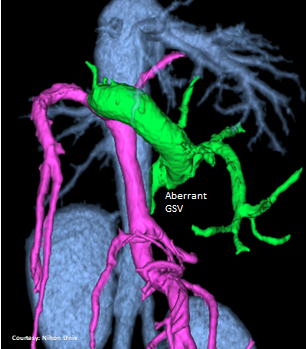

“aLGP”

Aberrant Left Gastro-Phrenic Shunt

Courtesy: Nihon Univ